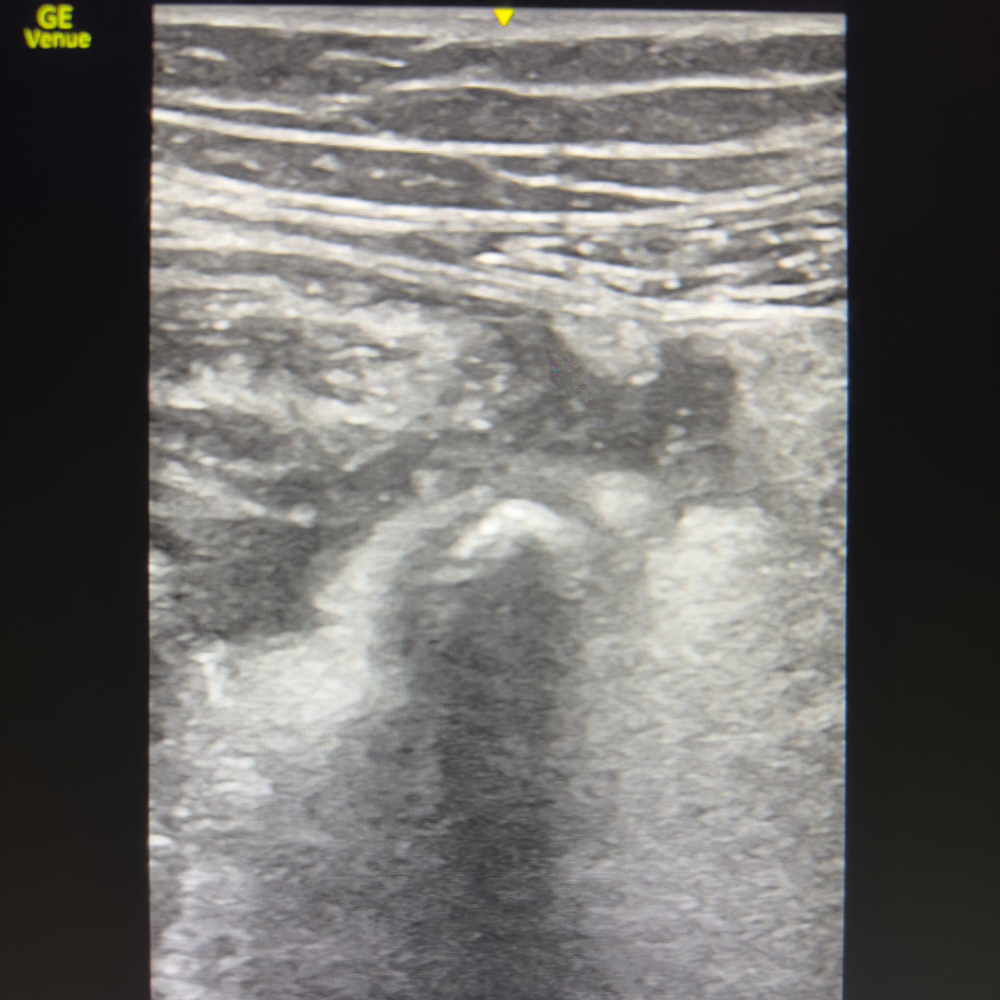

🧭 Technique

📍 Point de départ : FID, coupe transversale

Placer la sonde en transversal FID.

Identifier les vaisseaux iliaques :

Structure ronde, anéchogène

L’artère est pulsatile

Confirmer au Doppler couleur si doute

Une fois les vaisseaux repérés, explorer en avant et médialement :

👉 Chercher une structure :

Tubulaire

Non compressible

Non pulsatile

Sans péristaltisme

L’appendice se projette classiquement antéro-médialement aux vaisseaux iliaques.